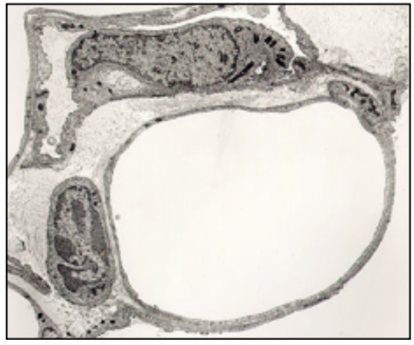

ENDOTHELIAL CELLS (EM)

- specialised - release vasoactive substances

- capillary @ centre

function:

- active transport of molecules across cytoplasm

- influence muscle tone

- coagulation

- produce cell adhesion molecules - influsence lymphocyte/neutrophil migration